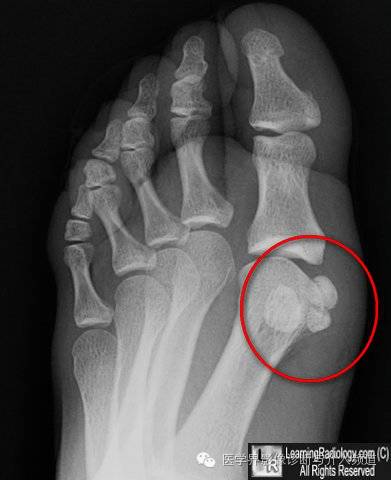

10、籽骨:籽骨为受压较大的肌腱内生成的中小骨块,具有辅助活动的功能,常见于手、足部。